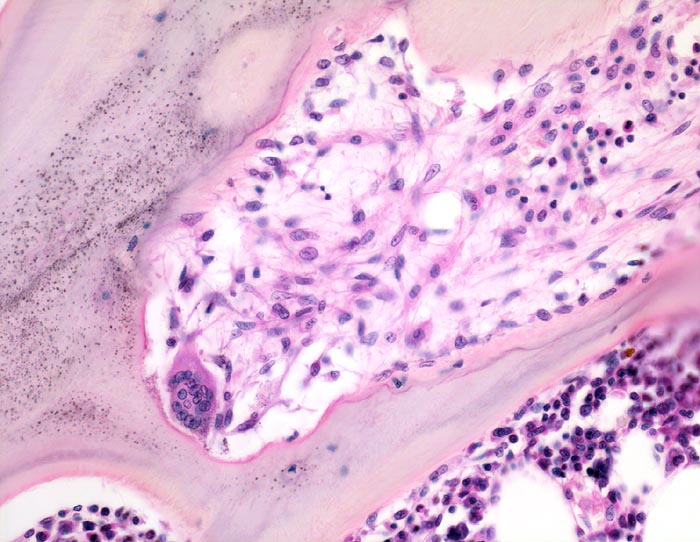

Fibroosteoklasie: Resorptionslakune

Spongiosabälkchen mit tiefer Resorptionslakune, die das Bälkchen tunnelartig aushöhlt. In dieser Lakune links unten im Bild ein Osteoklast mit >10 Kernen/Schnittebene. Parallel zur Spongiosaoberfläche vermehrt Osteoblasten. Die Resorptionslakune ist aufgefüllt mit lockerem Bindegewebe gebildet von Fibroblasten.

Adenom der Nebenschilddrüse mit primärem Hyperparathyreoidismus. Nephrolithiasis.